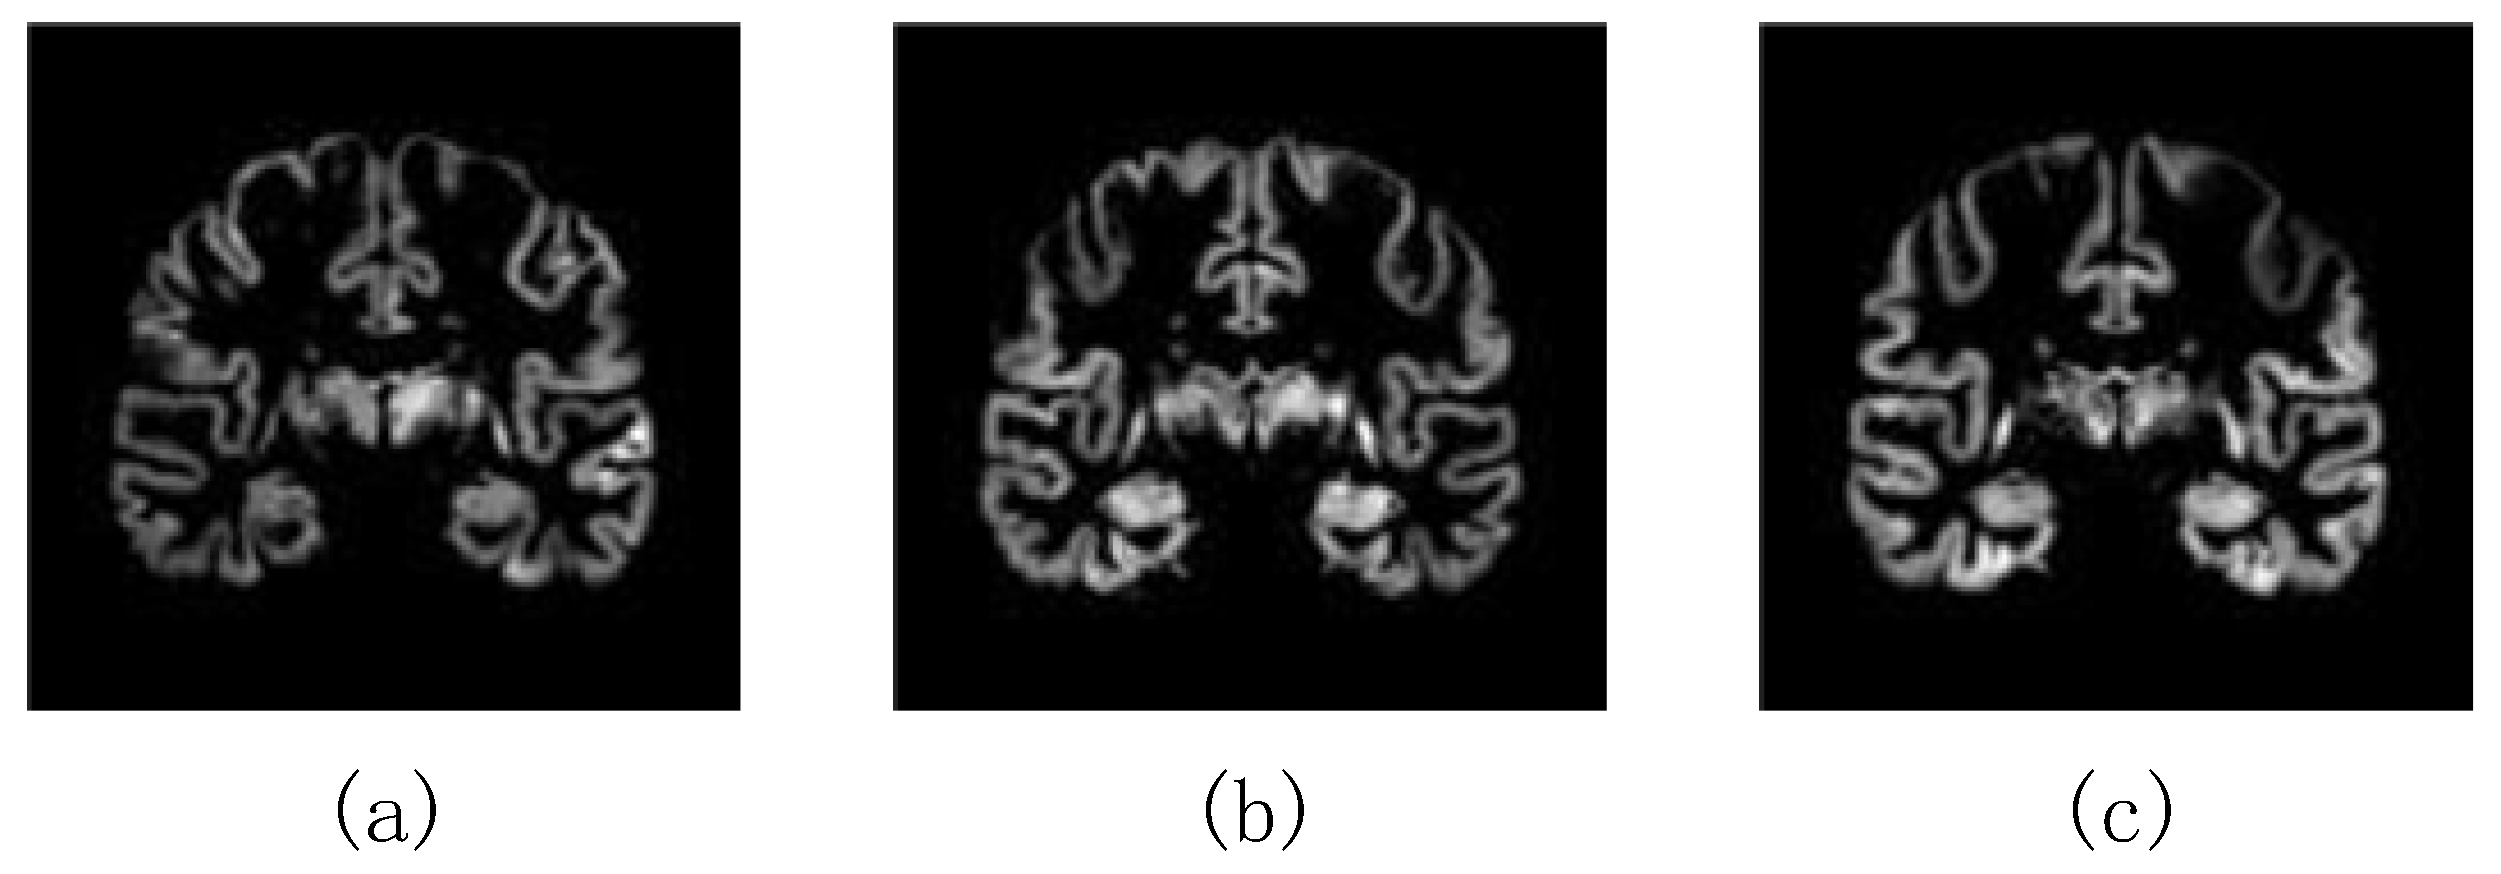

3.2.2. The Choice of the Most Informative Slices